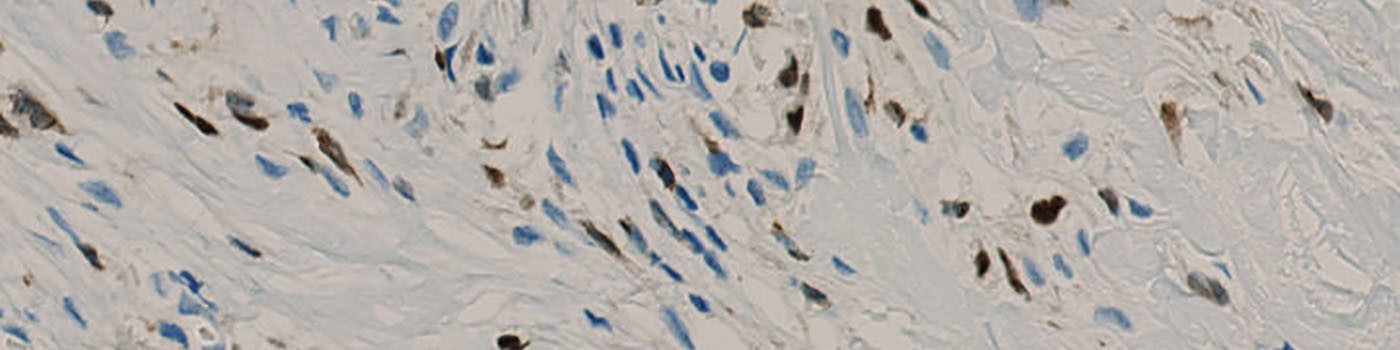

Original Image at 1x after the tissue automatically has been segmented and outlined as ROI.

The first image processing step involves a segmentation of background, tissue, negative and 5LO positive nuclei (see FIGURE 3). Next a post-processing step is applied to remove background, tissue and negative nuclei (see FIGURE 4). Additionally, 5LO positive nuclei are separated into two groups based on their area (below and above 10 µm2) and nuclei with a too low staining intensity are removed. The image obtained after post-processing (see FIGURE 5) is used to determine the output variables.

Tissue is outlined as ROI automatically using an auxiliary APP. It is possible to modify the ROI outline with the layer drawing tool. This may be necessary if damaged tissue is present in the ROI.